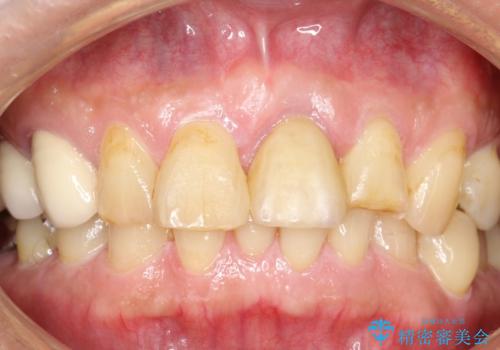

[ セラミック・インプラント全顎治療 ] 長年悩まされている歯の治療にケリをつけたい